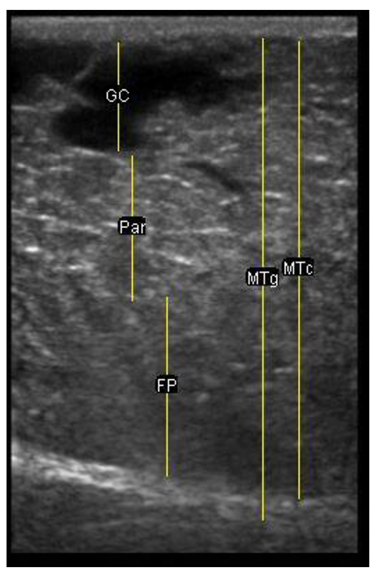

| 113 days of pregnancy (P113) Scanning depth 4.7 cm | ![]() | ![]() | MT generous: 28.9 mm MT conservative: 25.9 mm Gland cistern: 3.3 mm Parenchyma: 10.9 mm Fat Pad: 10.0 mm |